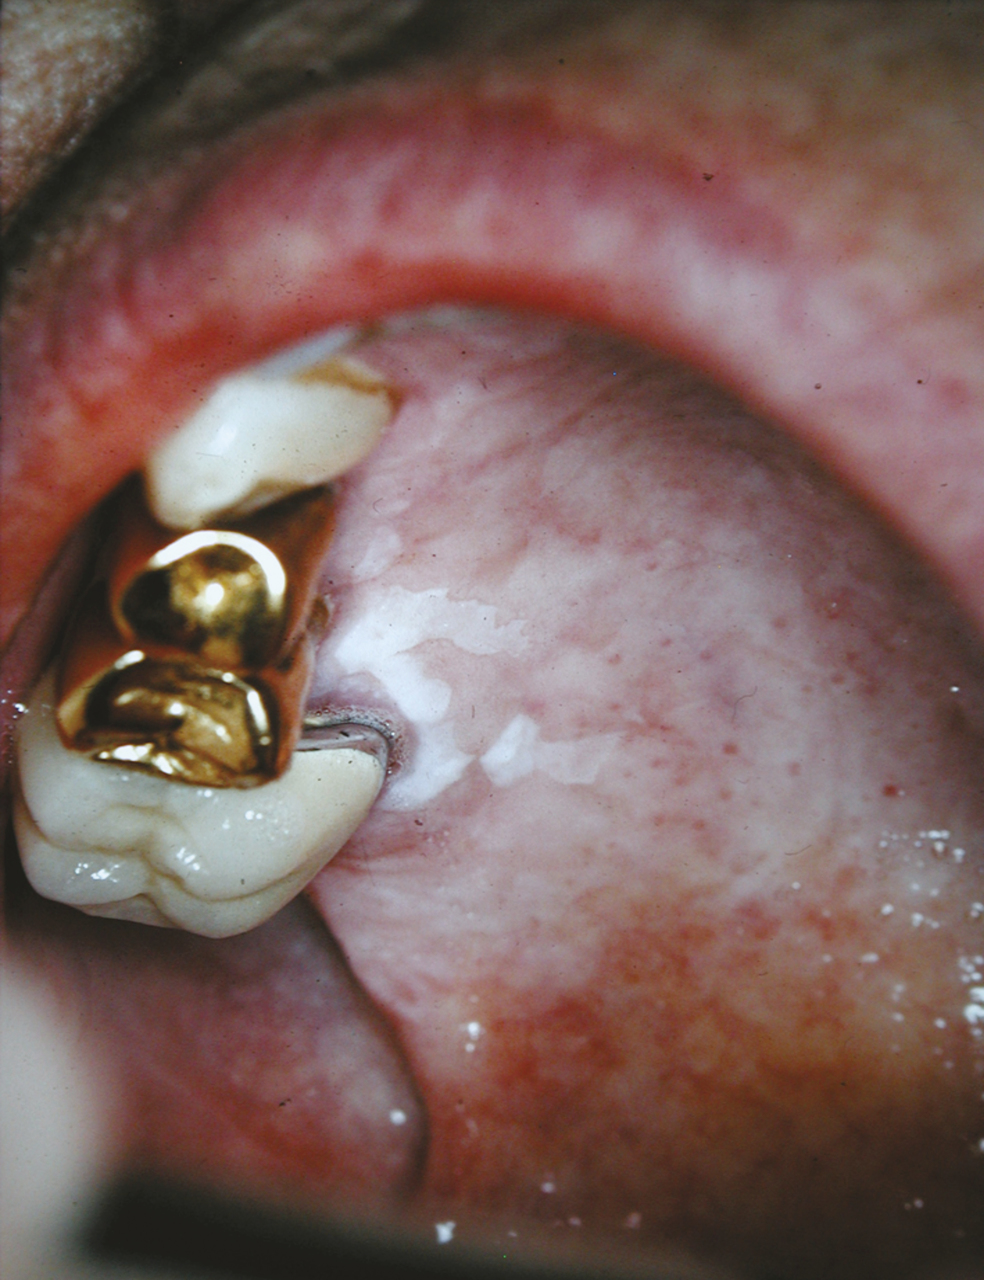

Le lichen plan et les lésions lichénoïdes (fig. 9 ) ont des caractéristiques cliniques et histologiques permettant habituellement de les distinguer des leucoplasies. La biopsie est donc nécessaire. La distinction entre le lichen plan et les lésions lichénoïdes est du domaine du spécialiste ; elle peut être importante dans la mesure où seules les lésions lichénoïdes seraient susceptibles de transformation maligne.4

Le lichen plan et les lésions lichénoïdes (